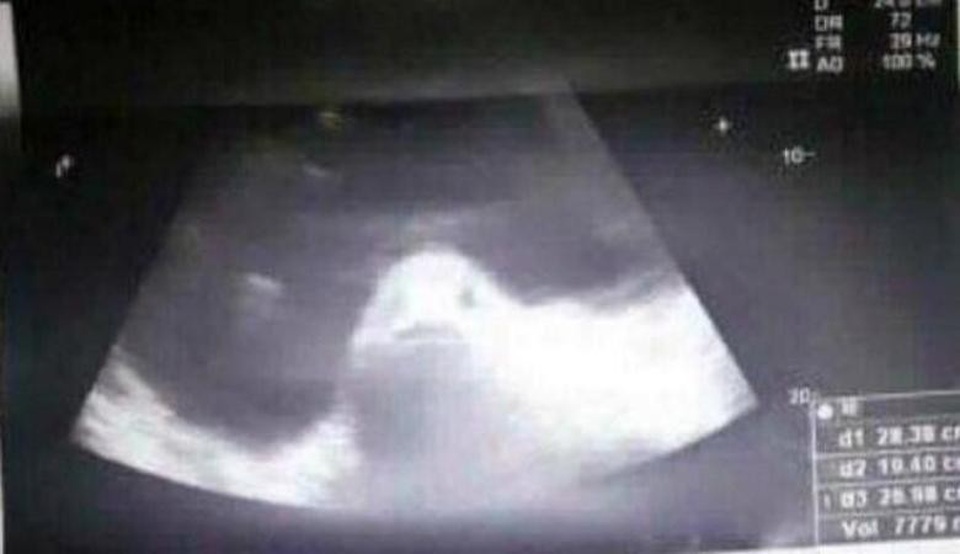

Họ buộc Kimberly phải tiến hành siêu âm nhưng hình ảnh xuất hiện lại giống như một sinh vật kỳ lạ có đôi mắt và miệng cá. Kimberly cho biết dựa trên những câu chuyện dân gian Philippines và tình yêu bơi lội khỏa thân của trẻ em nơi đây mà gia đình cáo buộc rằng cô đã có quan hệ tình dục với một con cá.

Tiến sĩ Massachusette Fernandez, bác sĩ phụ khoa đang điều trị cho Kimberly cho biết: “Ảnh siêu âm thực sự giống như một con cá nhưng nó không phải là con cá. Cô bé bị u nang buồng trứng. Không thể có một con cá bên trong buồng trứng của cô bé được”.